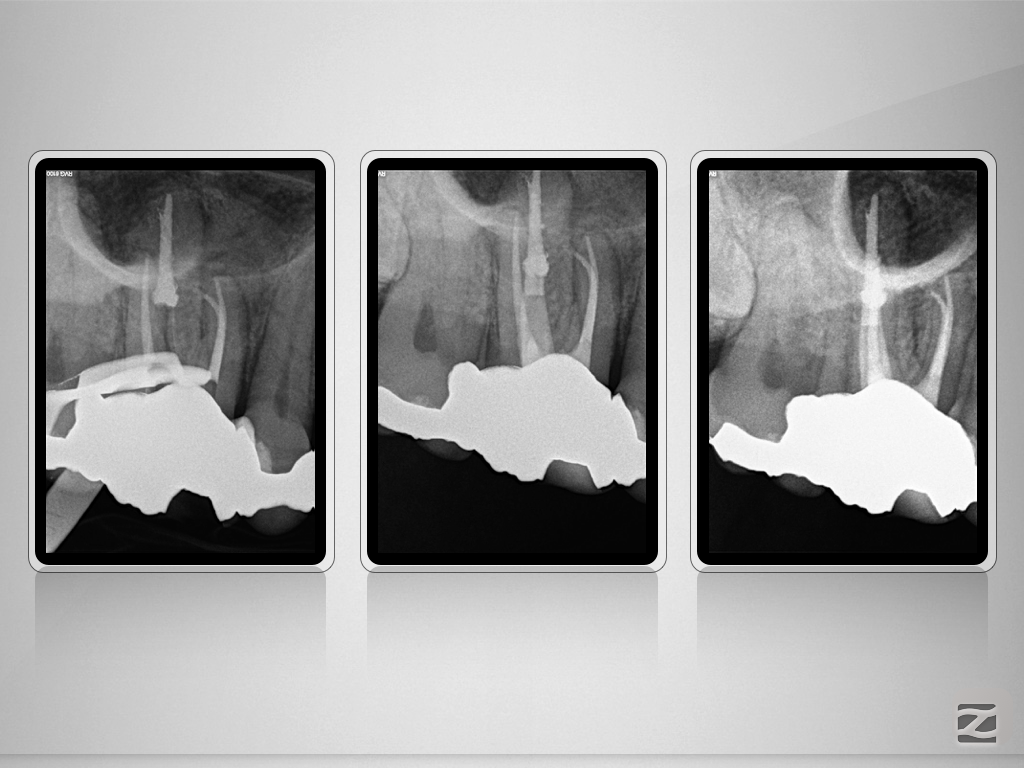

16D.018

Immer schön skeptisch bleiben 4